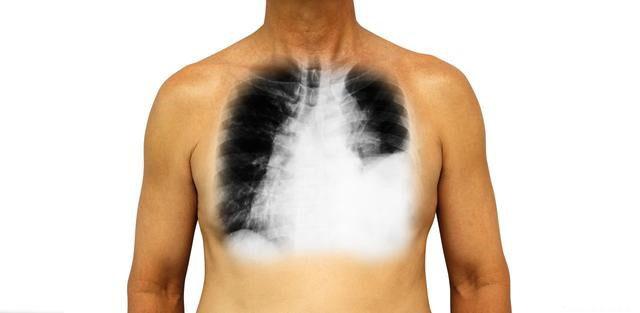

临床上,很多肿瘤患者到晚期会经历疼痛、腹胀、胸闷气喘等各种症状。不少患者会出现不同部位积水,比如腹腔积液,胸腔积液,心包积液等。当出现腹腔积液时,表现为腹胀,疼痛,食欲差,呕吐等症状,当出现胸腔积液或者心包积液时,病人可能会有胸闷,气喘,呼吸困难,甚至心肺功能衰竭。胸腹水主要特征为增长迅速,多为血性,穿刺放水后,有迅速再增加的倾向,利尿剂治疗效果不佳,临床治疗比较困难。为什么晚期患者会有各个部位的积水出现?

3.癌栓阻塞或肿块压迫 当肿瘤增长巨大,会引起循环障碍,当血管内压力过高时,可引起静脉血管床充血,静水压增高,致血管内外液体交换失衡,组织液回吸收减少而漏入胸腹腔引起积水。比如原发性肝癌或者肝转移癌,由于肝硬化或者门静脉癌栓引起门脉高压,会出现大量腹水。肺癌晚期患者当胸膜转移结节侵犯和阻塞毛细血管和淋巴管会引起大量胸水。一般来说,肺腺癌发生胸水腹水比较多见,这是因为肺鳞癌在局部生长较多,而肺腺癌容易出现血行转移。

4.抗利尿激素增多 多种恶性肿瘤均可引起抗利尿激素综合征,在肿瘤临床中较为常见,如肺癌,胰腺癌,脑瘤,血液肿瘤等,尤其以小细胞肺癌(SCLC) 最为多见。表现为水潴留,尿钠排出增多,水排出少引起浆膜腔积水。